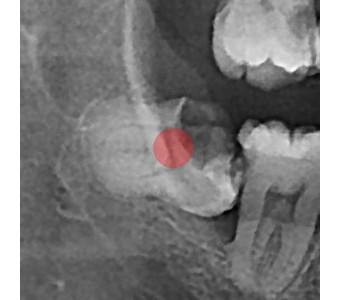

결과로 증명합니다.

국제모아치과의

실제 임상 증례